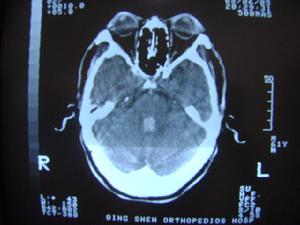

以冠狀動脈空氣栓塞常見,表現為術中心電圖一過性ST段抬高或心動過緩。其發生與手術操作有關,由於心房壓較低,輸送鞘送至左房後,空氣可進入左房,應在輸送鞘尾端有血液流出時再推送封堵器。其次為腦栓塞,可導致偏癱等嚴重後果。腦栓塞的發生與封堵器置入後局部繼發血栓形成有關,術後嚴格的抗凝及抗血小板治療是預防術後栓塞性併發症的關鍵。